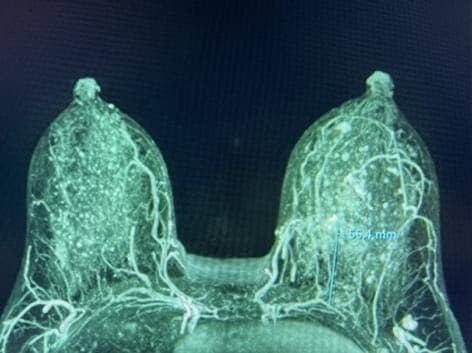

Şekil 1. MRG MIP, NAC'ye seyahat eden, meme başından üstün (solda) ve meme başı seviyesinde (sağda) IMP'leri gösterir.

Birden fazla dilimin ortalamasını alan yaygın bir yeniden format olan meme MRG MIP (maksimal yoğunluk projeksiyonu) görüntüleri, NAC'ye baskın kan akışını açıkça görselleştirdi (Şekil 1). Bilateral dominant IMP'ler, 2. ve/veya 3. interkostal boşluklarda (ICS) sternal sınır boyunca pektoralis majör kasından yayılır. Daha sonra, damarlar memenin deri altı dokusunda öne doğru seyretti ve NAC'nin yakınında sonlandı.

Önemli NAC kan kaynağını korumak için IMP-NSM cerrahi tekniği, önemli adımları içeren daha önce yayınlanmıştır. 1, 11, 12 Kontrastlı meme MRG, preoperatif evreleme için elde edilirse, en iyi MIP görüntülerinde görselleştirilen NAC kan akışını açıkça gösterebilir. Bu, tipik olarak IMP'den iki taraflı olarak, genellikle sternal sınır boyunca 2. veya 3. ICS'den kaynaklanan baskın NAC kan kaynağını gösterir (Şekil 1).

2.-4. ICS, sternal sınırın 1 cm lateralinde cilt üzerinde işaretlenir, bu da ana IMP damarlarının tanımlandığı ve pektoralis majör kasının önünde korunduğu ortak alanları gösterir. IMP-NSM tekniği, meme MRG'si olmadan, bu olağan yerleri işaretleyerek ve daha sonra bu alanlarda dikkatli bir diseksiyon yaparak gerçekleştirilebilir; bununla birlikte, varsa, meme MRG görüntüleri IMP kan temini hakkında yararlı bilgiler sağlayabilir ve ameliyattaki yeri tahmin edebilir. IMP-NSM, NAC'ye baskın IMP kan akışını korumak olarak tanımlanır; bununla birlikte, teknik, ilişkili ACN duyusal dallarına ek olarak, sternal sınır boyunca görselleştirilen ve vasküler beslemeye katkıda bulunabilecek ek küçük baskın olmayan IMP damarlarının korunmasını içerecek şekilde gelişmiştir. (Şekil 1 ve 2).